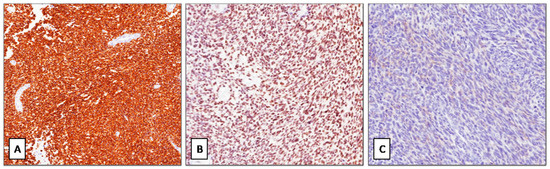

Desmoplastic Small Round Cell Tumor with “Pure” Spindle Cell Morphology and Novel EWS-WT1 Fusion Transcript: Expanding the Morphological and Molecular Spectrum of This Rare Entity

3.1. Histological and Molecular Findings